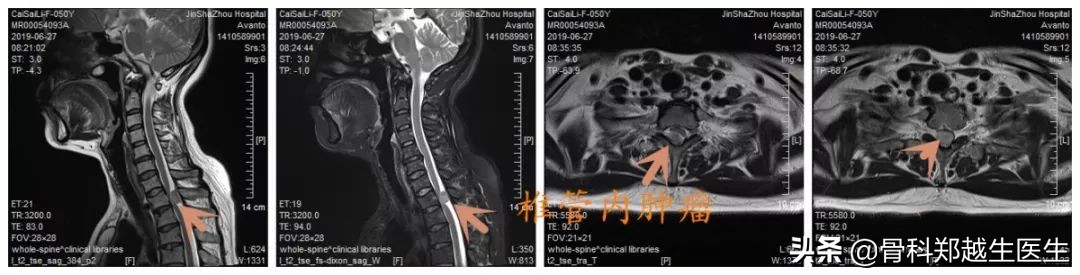

影像学检查提示:L2椎体压缩性骨折,L4椎体峡部裂并椎体滑移,T1椎体层面椎管内肿瘤。

患者诊断明确后,在我科行三期手术治疗,第一期,行腰椎经皮椎体成形术,术后腰部疼痛缓解,可坐起、站立行走。第二期,颈椎后路椎管内肿瘤摘除术,术后四肢麻木明显改善,肢体活动功能改善。第三期,腰椎后路椎间植骨融合椎弓根钉内固定术,术后患者可长时间站立、行走,生活基本恢复正常。